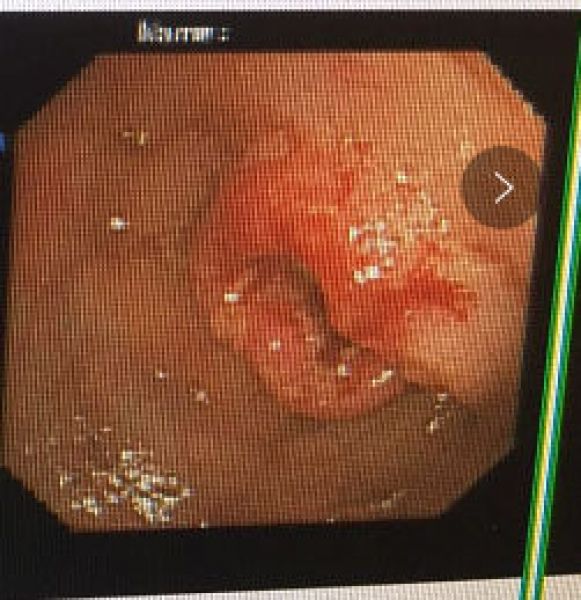

63岁男性田某,因肛门停止排气排便10余天拟肠梗阻收住消化二科。腹部CT提示肠梗阻、直肠乙状结肠占位,肠镜发现结肠距肛门19cm处有一新生物,管腔狭窄,活检提示低分化腺癌。根据病情,患者需行外科手术(一期造瘘,二期回纳),造瘘后需在腹壁挂着一个粪袋,既不便于生活,也不雅观,增加了病人的痛苦及经济负担。且该患者半年前因冠心病行了冠脉支架置入术,一直服用拜阿司匹林及氯吡格雷抗血小板药物,短期内不宜外科手术。经消化内科与普外科讨论后于4月23日在介入室成功置入肠道支架,肠道支架置入后即刻见粪便涌出,排气排便恢复。术后转外科行一期手术切除肿瘤。

肠镜下见结肠肿瘤 造影见肠腔狭窄,口侧肠管扩张